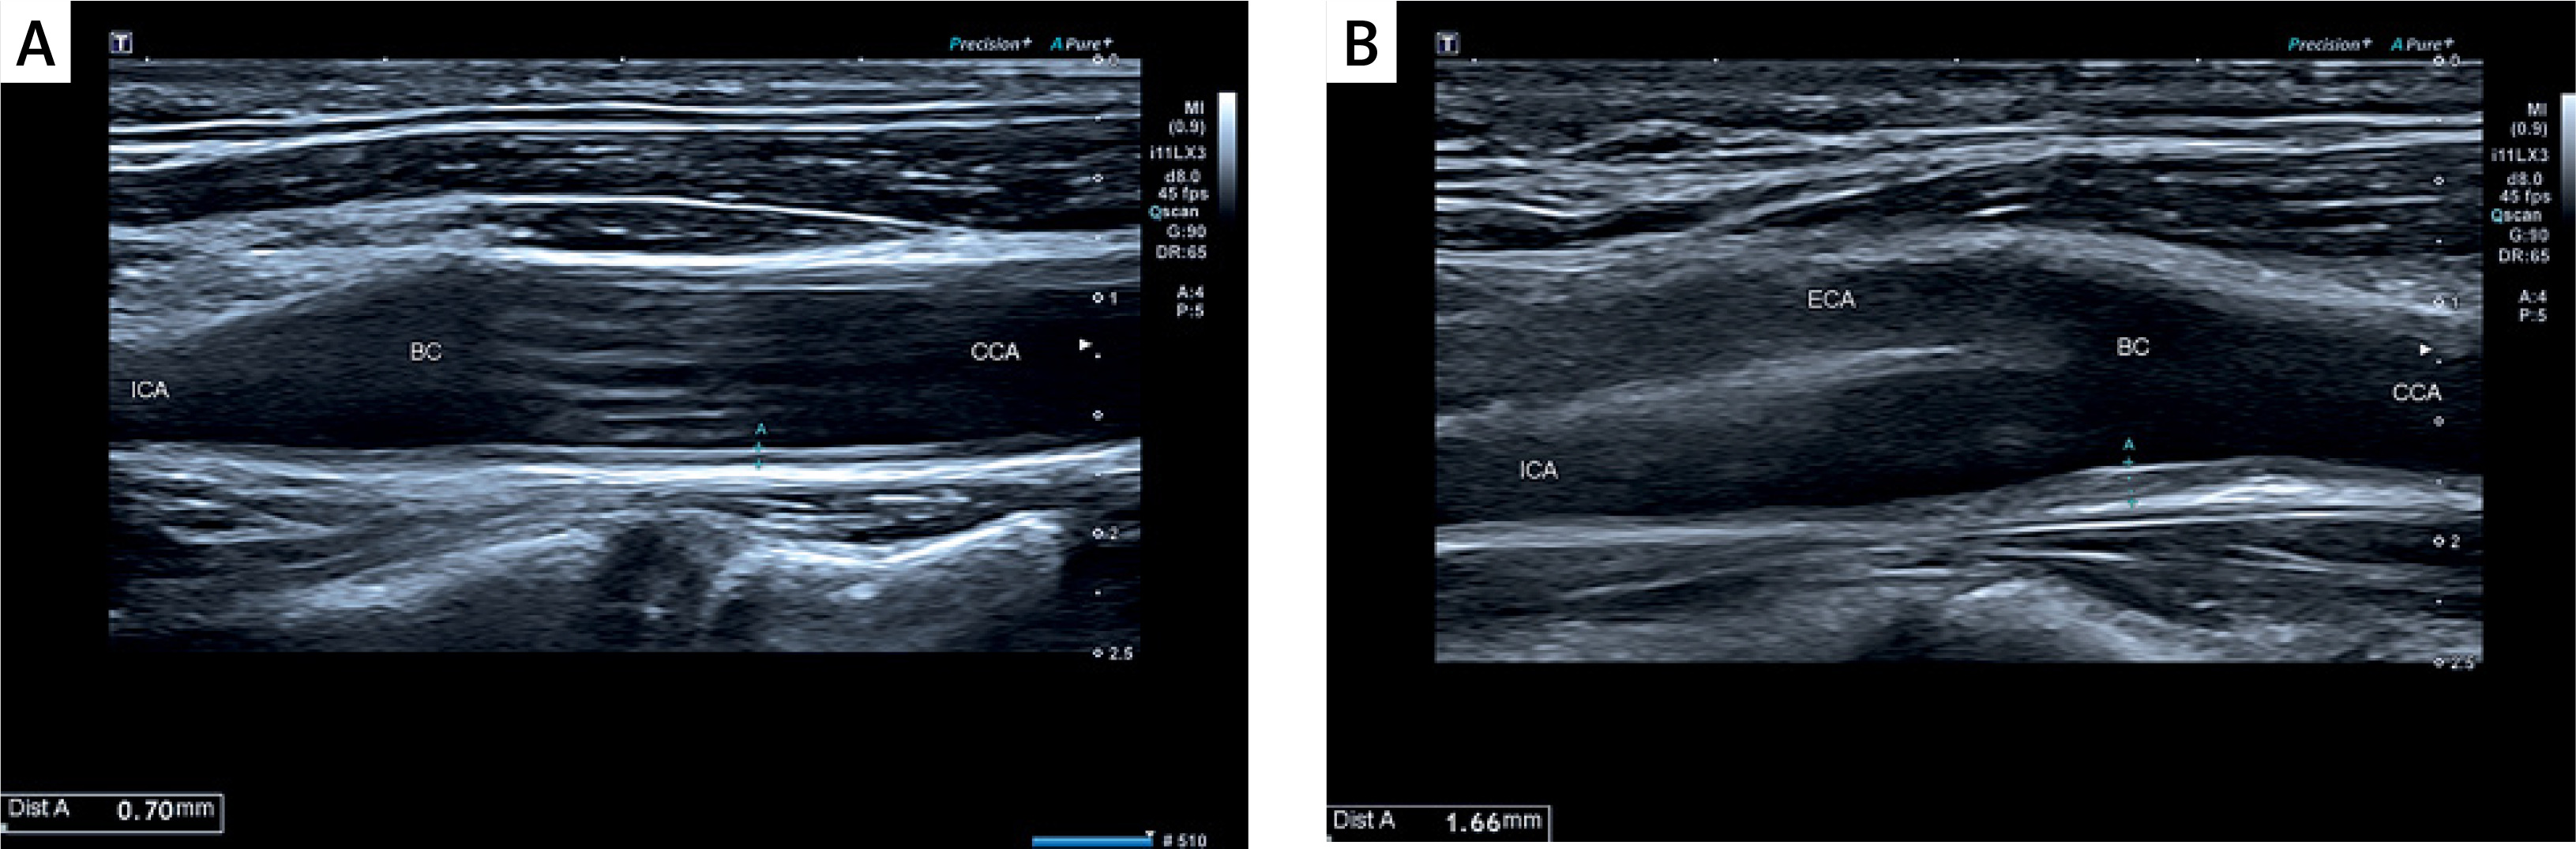

Among diagnostic procedures, the carotid and vertebral arteries’ morphology combined with intima-media complex characteristics was determined by an experienced ultrasonographer on the Philips EPIQ CVx system using a high-frequency broadband linear probe (3.0–12.0 MHz). CIMT measurements were performed on the posterior wall of the carotid artery 10–20 mm distally from the common carotid bulb.

The intima-media complex was routinely examined in ultrasound imaging, and patients were divided according to the CIMT 0.8 mm cut-off value, as presented in Figures 1 A, B.